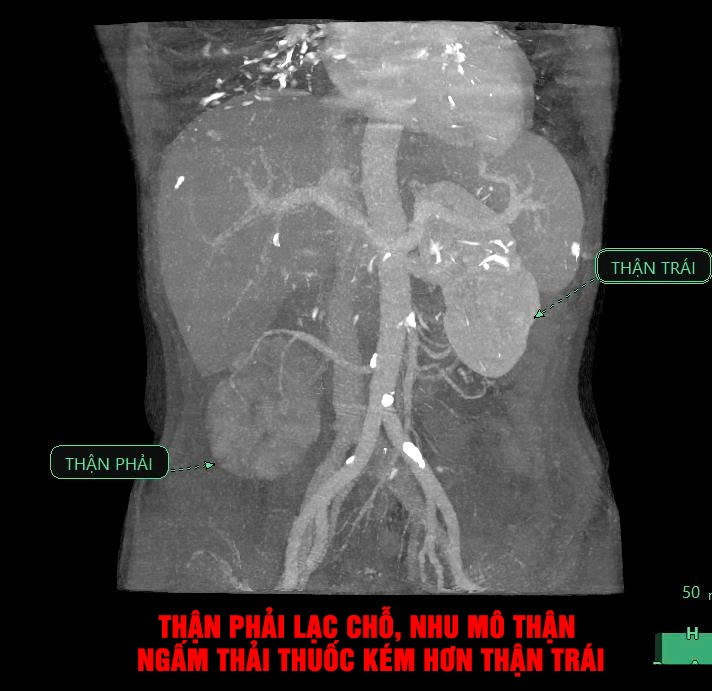

Các bác sĩ đã nhanh chóng thực hiện các cận lâm sàng cần thiết. Kết quả chụp CT-Scanner ổ bụng ghi nhận viêm thận – bể thận phải, thận phải lạc chỗ và giãn đài bể thận trái.

Hình ảnh chụp Cắt lớp vi tính có tiêm thuốc cản quang: Thận phải lạc chỗ, nhu mô thận phải ngấm thải thuốc kém hơn thận trái, bể thận xoay ngoài, nhu mô thận có hình ảnh các ổ không ngấm thuốc (quan sát rõ ở các thì tĩnh mạch và thì muộn) - Ảnh BVCC